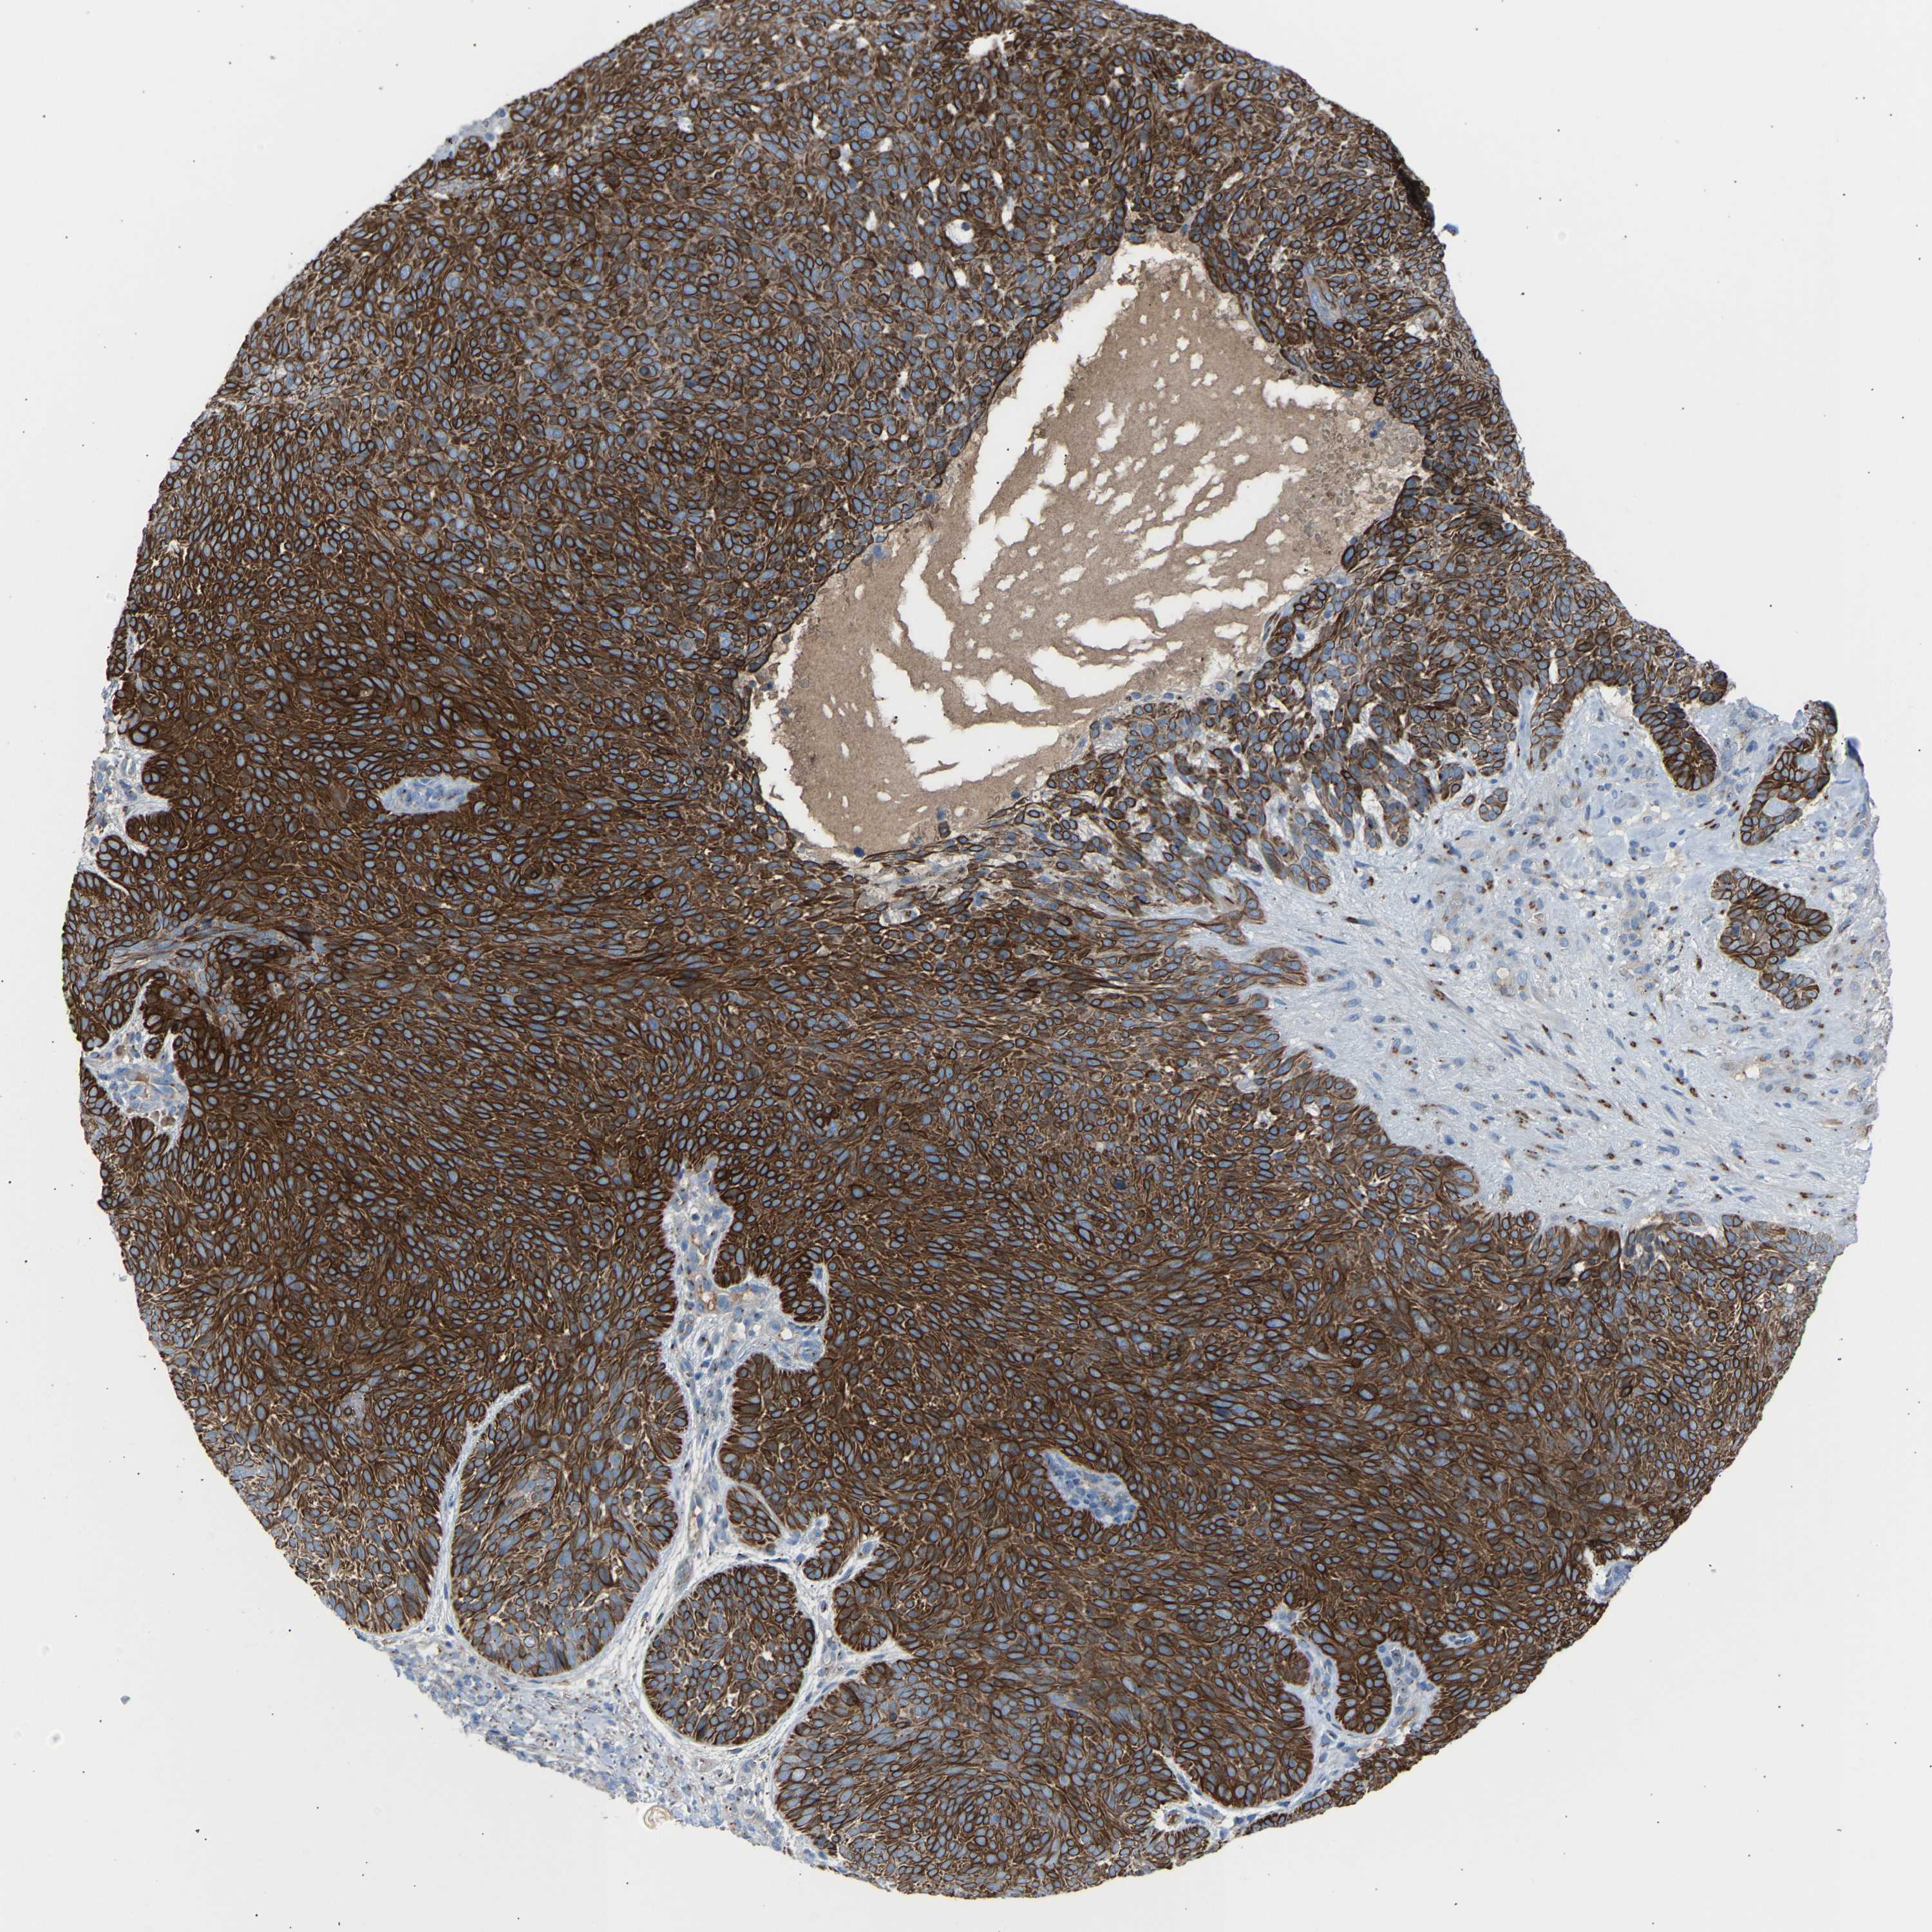

SKIN CANCER - Protein expressioni

A mouse-over function shows sample information and annotation data. Click on an image to view it in a full screen mode. Samples can be filtered based on level of antibody staining by selecting one or several of the following categories: high, medium, low and not detected. The assay and annotation is described here.

Each image is clickable and will lead to virtual microscopy that enables deeper exploration of all samples and also displays staining intensity scores, fraction scores and subcellular localization as well as patient and tissue information for each sample.

Antibody HPA020060

Squamous cell carcinoma, metastatic, NOS